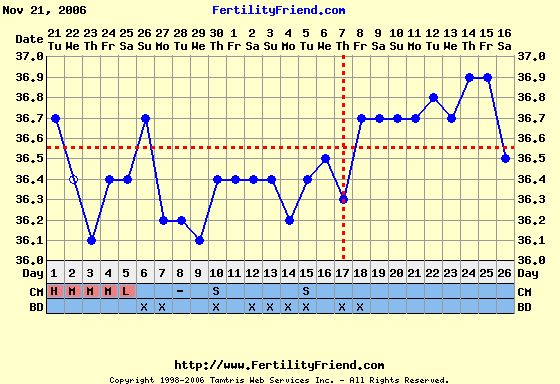

Éva, ez aztán a szép görbe! Igaz, én kicsi meglepődtem, hogy a 10. napon volt a pé-ed, de mivel nem esik vissza, tényleg akkor lehetett. Akkor viszont nemsokára tesztelhetsz!

Verzsike, szerintem ebből a görbéből még akármi lehet. A legjobb egy + volna a tesztek sávjában!

Ez a leesés akár beágyazódás is lehetett!!!

Addig is a semleges görbém.